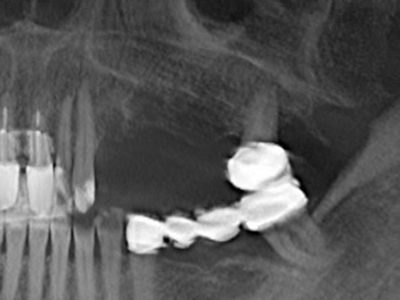

Purely orthodontic indications include orthognathic surgery, genioplasty (Fig. 27-30) and orbital decompression in patients with advanced endocrine orbitopathy as a result of Basedow’s disease (Ponto, Zwiener et al. 2014). Piezo devices are also used in maxillofacial surgery and to remove tumours at the base of the skull in various hospitals.